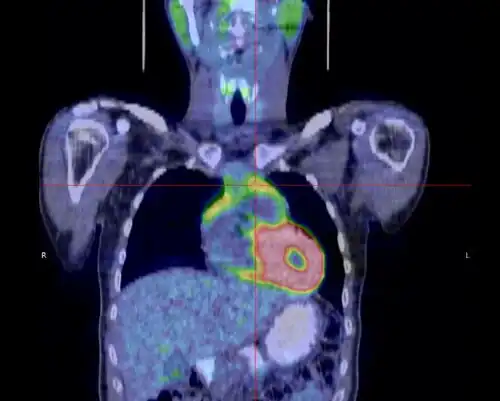

- Thymome de type B1 en TEP scanner

Coupe transversale. Les trois clichés sont extraits du même examen.

Coupe frontale ; la tumeur est à l'intersection des lignes rouges.

Coupe sagittale ; la tumeur est à l'intersection des lignes rouges.